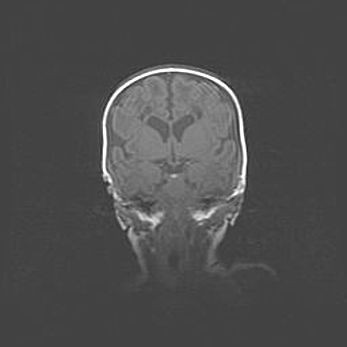

Наружная гидроцефалия с возможной атрофией височных областей.

Возраст: 28 дней

Вес: 3670 г

Пол: мужской

Окружность головы: 38 см

Срок гестации: 40 недель

Гидроцефалия головного мозга у новорожденных – это заболевание, которое характеризуется скоплением избыточного количества спинномозговой жидкости в желудочковой системе головного мозга в результате затруднения её перемещения от места выработки к месту поглощения в кровеносную систему или вследствие нарушения абсорбции. При открытой наружной форме гидроцефалии у новорожденных расширяются и переполняются субарахноидные пространства.

При нормотензивных  формах,  которые,  как  правило,  являются  следствием  перенесенных ишемических  повреждений  паренхимы  мозга,  возможно  сочетание микроцефалии  с нормотензивной гидроцефалией. В основе данных изменений лежит атрофия больших полушарий с преимущественной  локализацией  в  лобно-височных  областях.